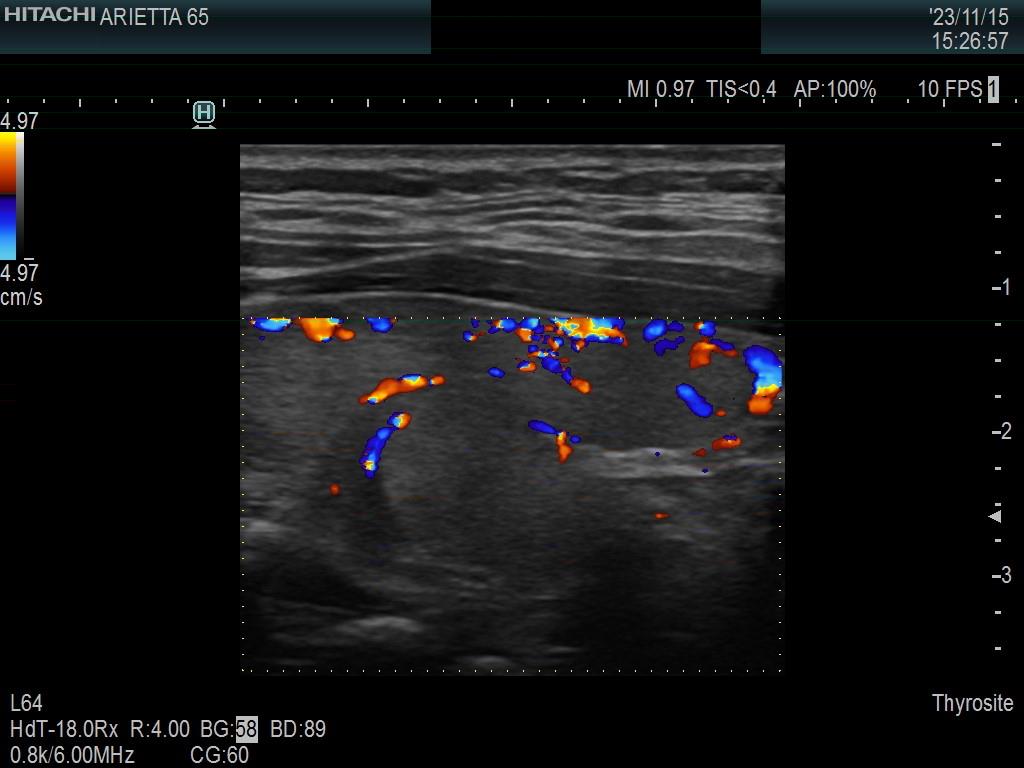

Left lobe, longitudinal scan, color Doppler mode. There is a vessel according to the upper hypoechoic area.